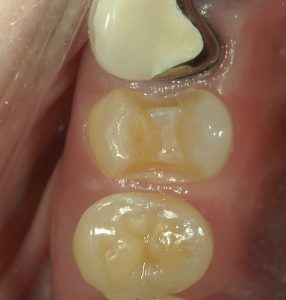

3 MTA系神経保護材

ケイ酸カルシウム覆髄材というものを用い、歯の神経を保護します。カルシウムイオンと水酸化物イオンが放出されることによりアルカリ環境がつくられ、デンティンブリッジ形成を促します。

上の写真では神経近くまでむし歯が進行していたため、このMTA系神経保護材を用い歯髄(歯の神経)保存治療を行なっています。

精密審美治療+歯髄保存治療

上記のように神経を保護した後、歯を長持ちさせ、歯・からだ・笑顔に優しい精密な審美治療を行います。